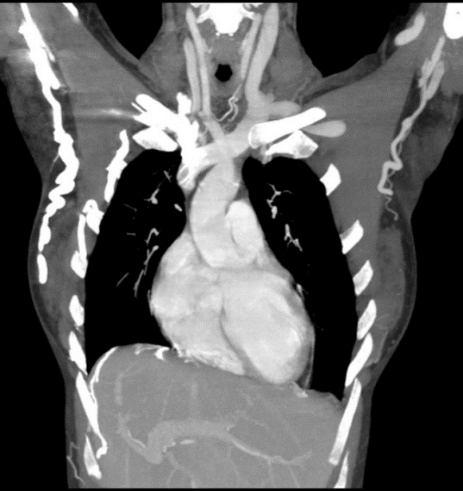

A 28-year-old lady a known case of celiac disease with persistent hypocalcemia refractory to oral calcium replacement therapy. So, she frequently received calcium gluconate through the right jugular venous catheter for about 4 weeks. Afterwards she developed facial swelling, plethora, headaches, dry cough and orthopnea. There was dizziness and head spinning sensation on bending the head forwards. Examination showed distended neck and upper trunk veins. CT angiogram revealed complete obstruction of SVC and formation of upper trunk venous collaterals. (Figure 1).

Figure 1: CT scan Thorax (Coronal view) showing complete obstruction of SVC.